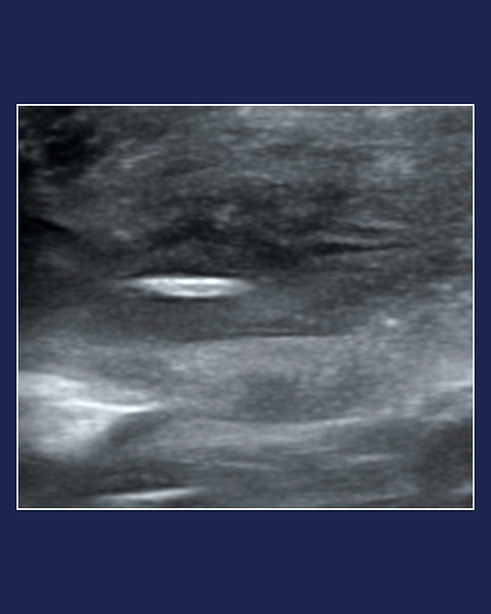

Ultrasound Guided Procedures

Real-time ultrasound guidance for minimally invasive diagnostics and selected treatments.

What we support (case-dependent):

-

Fluid procedures: thoracocentesis, abdominocentesis; pericardiocentesis when appropriate

Targeted aspirations: cyst/abscess aspiration; cystocentesis

Foreign body localisation/removal (e.g., grass seed)

FNAs of lymph nodes: e.g., medial retropharyngeal, cervical (superficial/deep), axillary, superficial inguinal, colic/jejunal, hepatic, medial iliac

Targeted organ sampling: gastric/intestinal wall, liver, kidney, spleen, adrenals, and soft-tissue masses

How it works: Case review → aseptic prep & sterile probe cover → real-time needle targeting → smear/handling tips → post-procedure scan; samples go to your preferred lab.